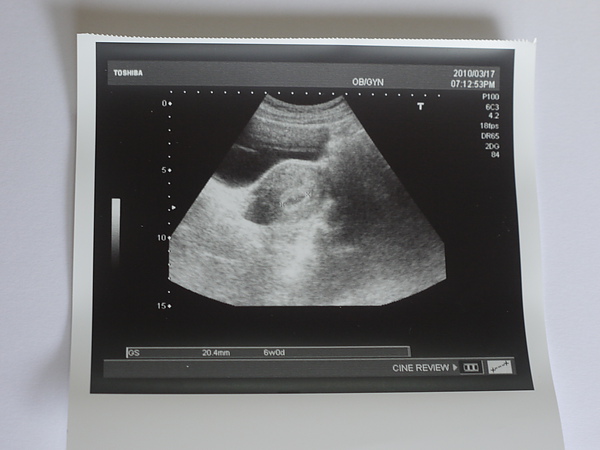

這張超音波,就是證明虎妹真的是虎妹,不是虎弟,

I really got a baby gril, not a baby boy.

虎妹的二腿之間,真的沒有別的器官,沒有family jewelry.

記得在三月時,P去了一趟新加坡,有大半月都不在台灣,

趁著他在國外的時候,自已獨自跑去檢查,

結果,就帶了這一張回家!